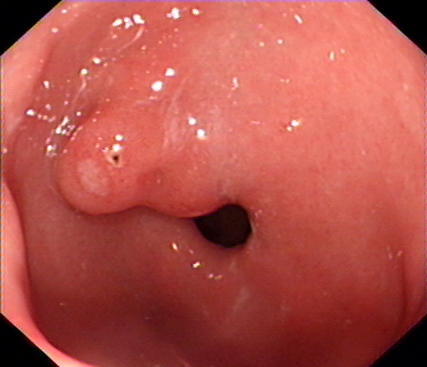

我们再来看一组胃镜图片,由胃溃疡到胃癌的过程(图片来源于网络)。患者未按医生医嘱,定期复查胃镜活检,最后进展为晚期胃癌。

消化内镜是目前发现消化道肿瘤的有效手段。胃肠镜检查通常可发现可疑病变,进一步行精查内镜,通过图像增强内镜(电子染色或染料染色内镜)、结合放大等加以观察分析,判断病变的性质、边界范围判定、分化程度及浸润深度,不仅大大提高了早期消化道癌的检出率,并且可以评估病变是否适合内镜下治疗。内镜微创治疗,内镜下粘膜切除术(EMR)、内镜下粘膜剥离术(ESD)等是切除早期癌变组织,实现临床治愈的有效方法。